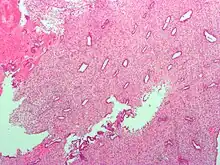

Low magnification micrograph of decidualized endometrium. H&E stain

The endometrium consists of a single layer of columnar epithelium plus the stroma on which it rests. The stroma is a layer of connective tissue that varies in thickness according to hormonal influences. In the uterus, simple tubular glands reach from the endometrial surface through to the base of the stroma, which also carries a rich blood supply provided by the spiral arteries. In women of reproductive age, two layers of endometrium can be distinguished. These two layers occur only in the endometrium lining the cavity of the uterus, and not in the lining of the fallopian tubes.[4][5]

If there is inadequate stimulation of the lining, due to lack of hormones, the endometrium remains thin and inactive. In humans, this will result in amenorrhea, or the absence of a menstrual period. After menopause, the lining is often described as being atrophic. In contrast, endometrium that is chronically exposed to estrogens, but not to progesterone, may become hyperplastic. Long-term use of oral contraceptives with highly potent progestins can also induce endometrial atrophy.[13][14]